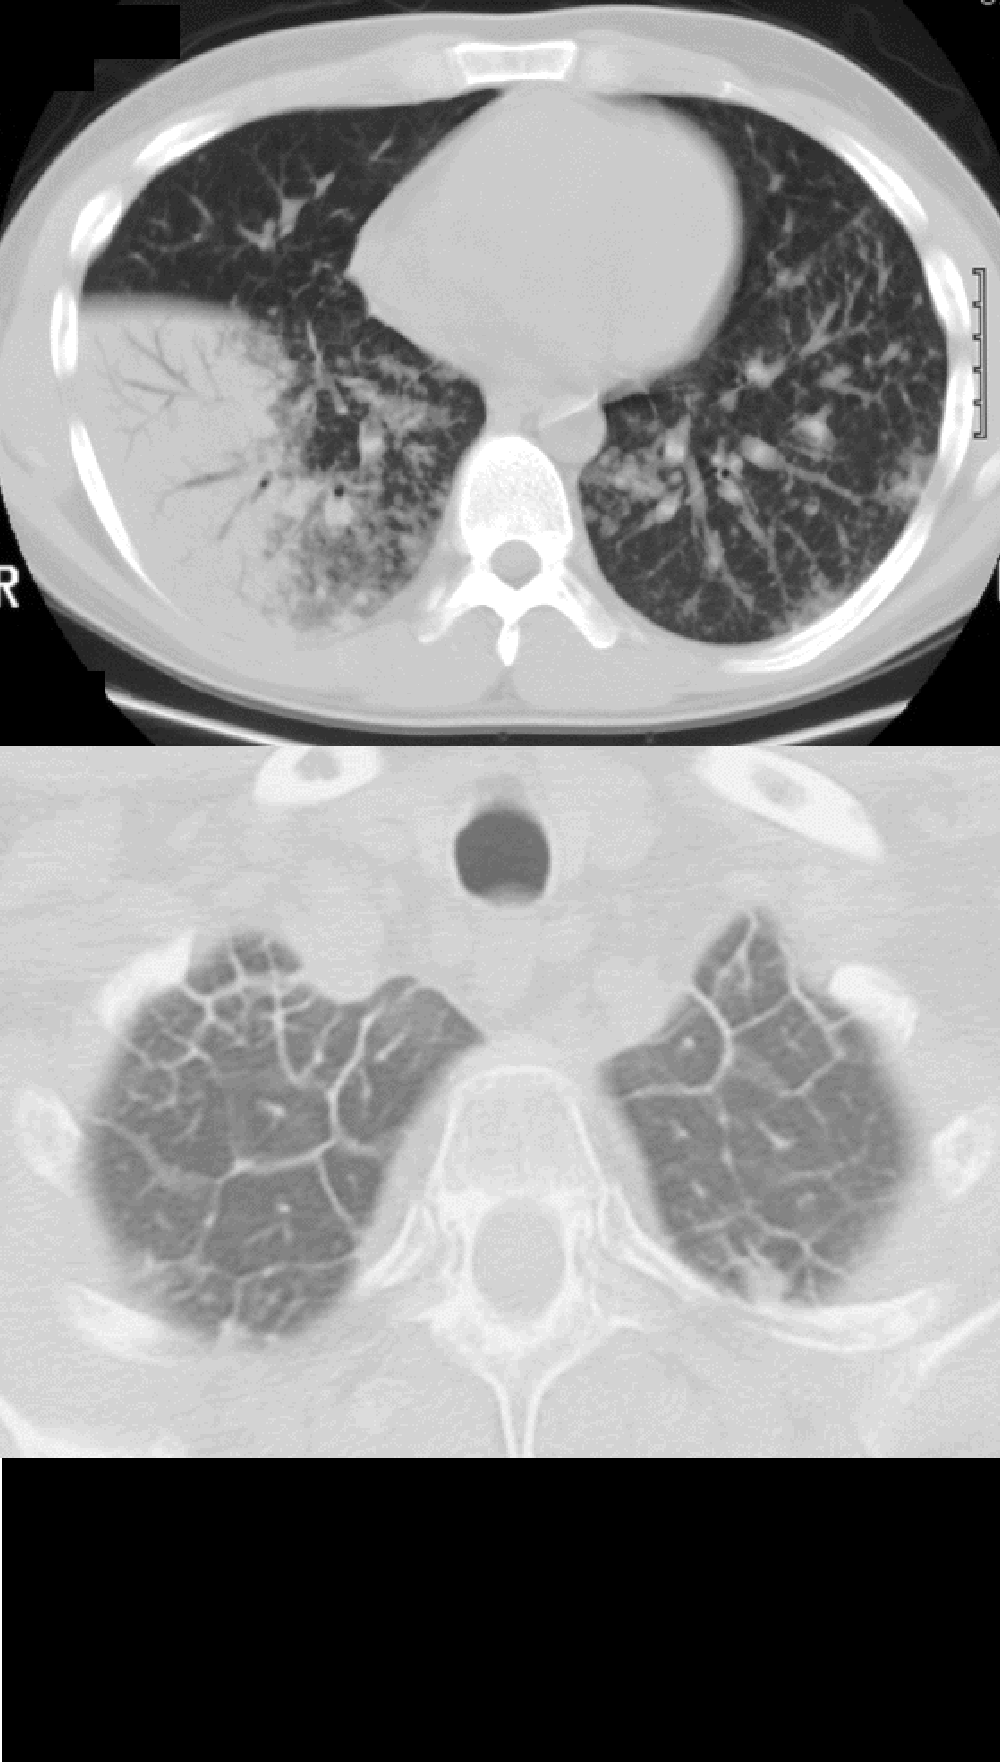

◂Chest CT for Internal Medicine Residents